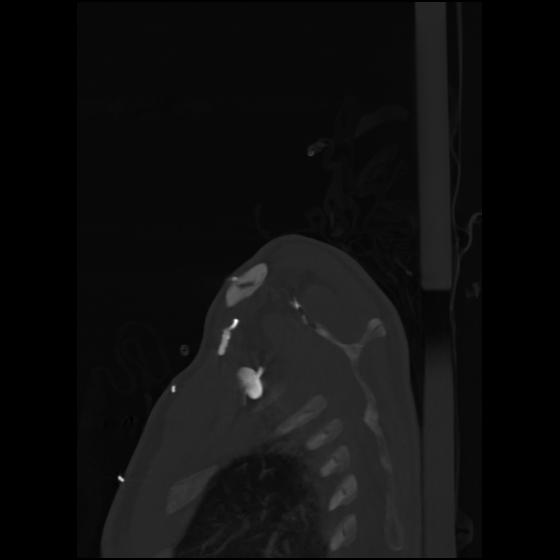

24 ANGIO,CE,Sag-MIP,5.000,ANGIO,Sag-MIP,